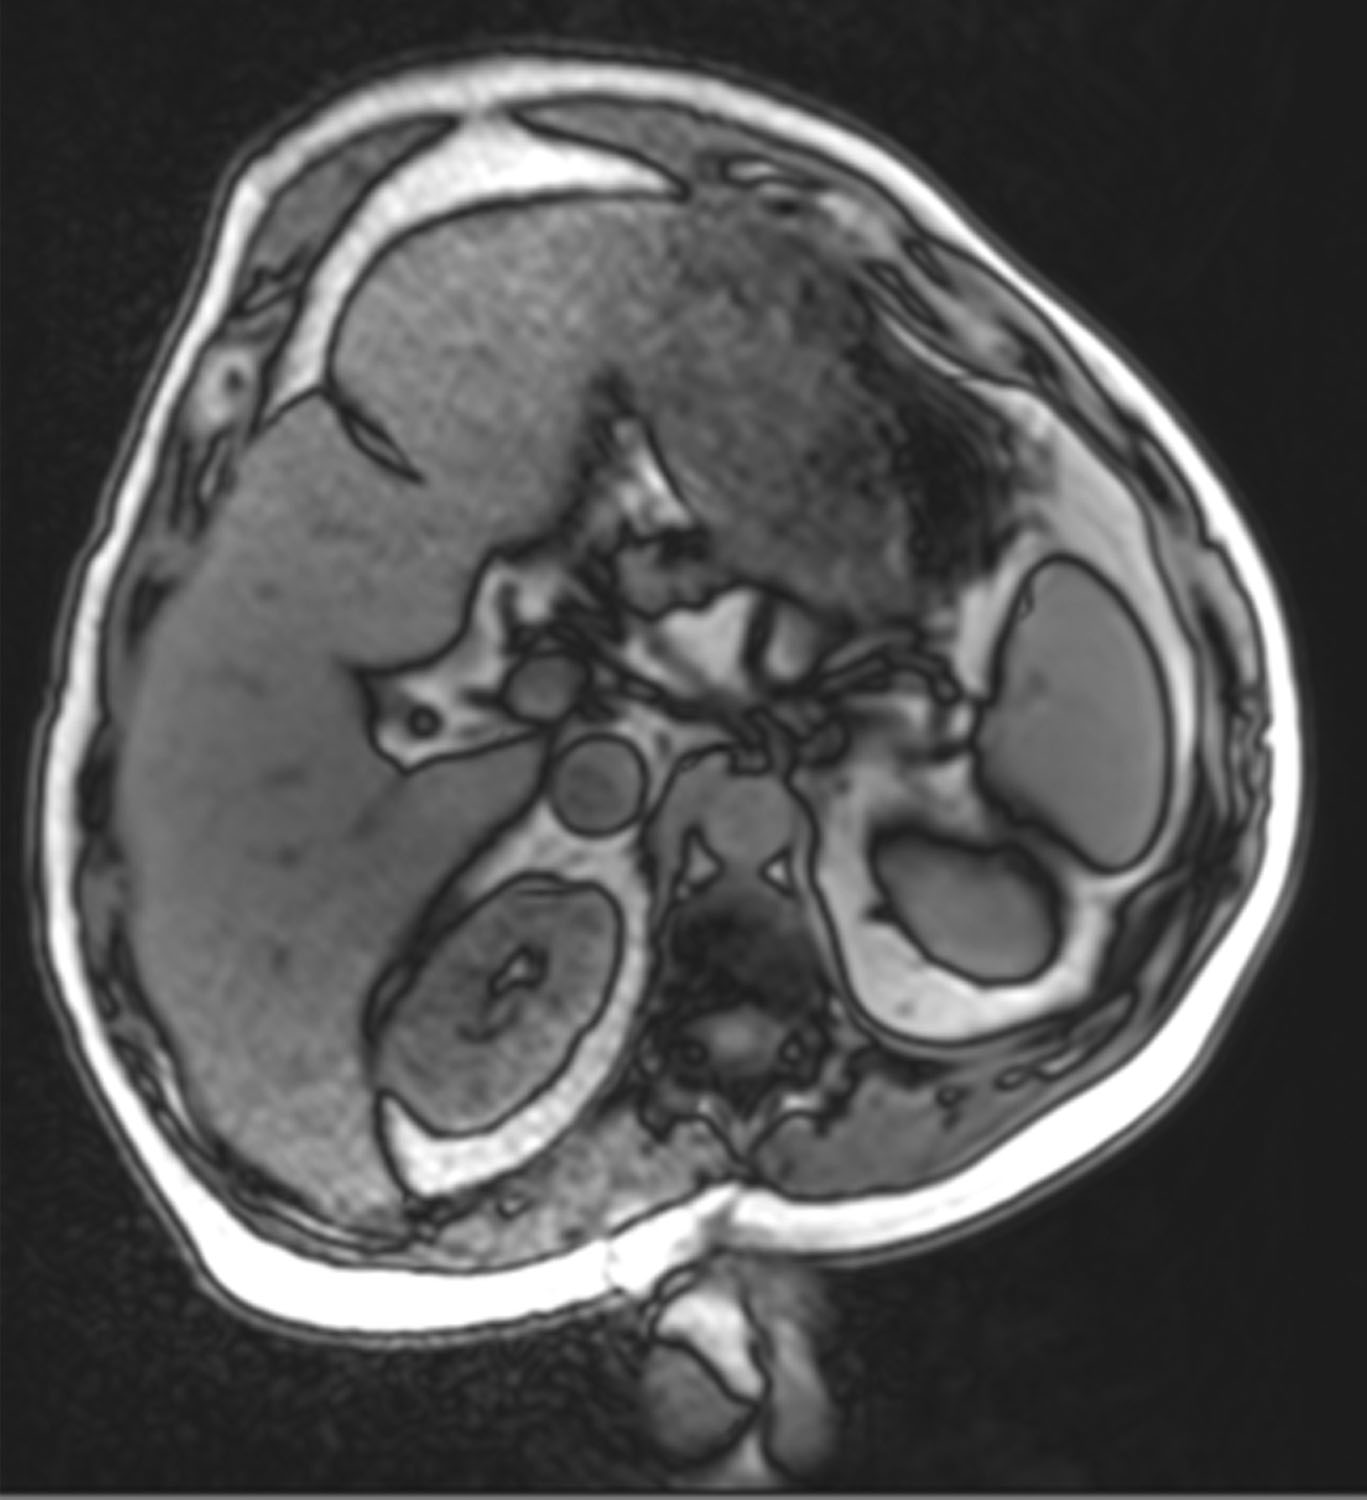

Figure 5. A-C. Wide-Rectus Abdominis Fascia Advancement from the axial view demonstrating recreation of a new linea alba via lateral anterior rectus sheath mobilization with re-approximation in the midline. Figure A demonstrates the native position of the lateral anterior rectus sheaths following incision. Figure B demonstrates medial mobilization of the anterior rectus sheaths medial to the linea semilunaris and reapproximating them in the midline, in order to create a new linea alba, as shown in Figure C.

Figure 24. Case 2: Magnetic resonance imaging taken in left lateral decubitus. Note the dysmorphic protuberant anterior abdominal wall preoperatively.

Figure 25. Case 2: Magnetic resonance imaging view shows the improved abdominal wall shape postoperatively along with the hypertrophied abdominal wall musculature.

Furthermore, we have noted hypertrophy of the abdominal wall musculature after tightening, as is supported in postoperative magnetic resonance imaging scans, which have demonstrated hypertrophied muscle along with an improved overall abdominal wall shape because of globally restored muscular tension. In parallel, Hicks et al noted muscular hypertrophy after the creation of a new linea alba following abdominal component separation.20 We theorize that this phenomenon is likely due to repositioning the muscle in a better position on the force/length curve, as discussed above.